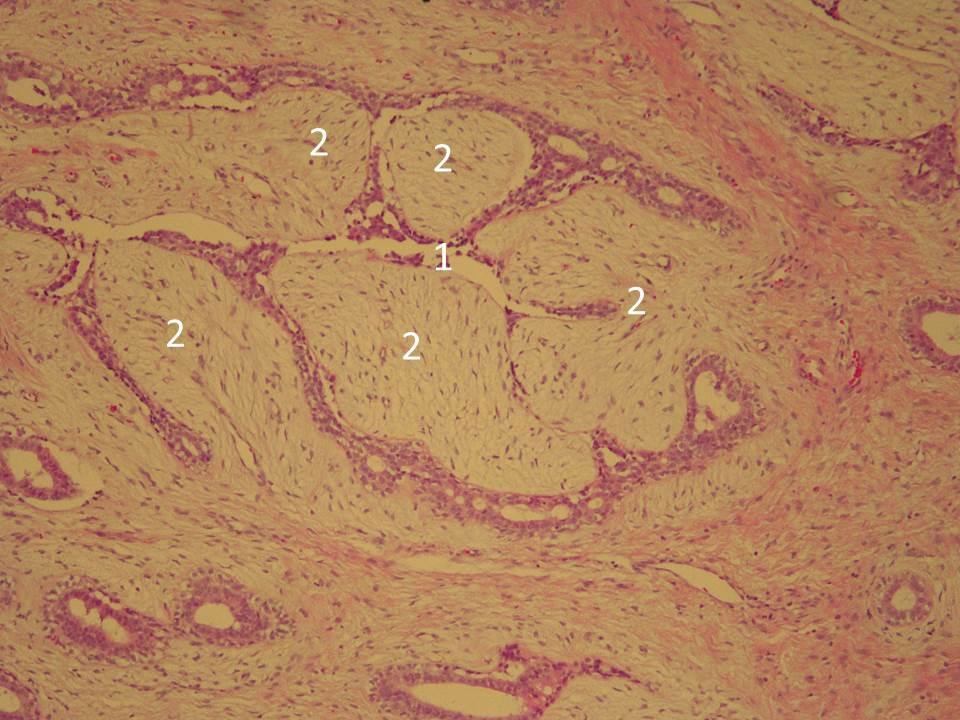

Исследование: микропрепарат молочной железы в медицине

Раздел: Снимки-откровения